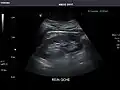

Abdominal Ultrasound (Full Exam)

STRUCTURED REPORT

(Technique: Transabdominal ultrasonography; Device: Toshiba Aplio XG)

Liver: Diffusely homogeneous and normal in echogenicity. No focal mass or contour nodularity. No intrahepatic biliary ductal dilatation.

Portal Vein: Patent main portal vein.

Gallbladder: No stones, wall thickening, or pericholecystic fluid.

Common Bile Duct: Nondilated measuring 1.3 mm at the level of the porta hepatis.

Pancreas: Visualized portions unremarkable.

Spleen: Normal in size.

Kidneys: Right and left kidneys measure 11.5 cm and 12 cm in length respectively. No hydronephrosis. Small left lower pole kidney cyst.

Ascites: None.

Aorta: Visualized portions normal in caliber, 16 x 15 mm.

IVC: Normal.

IMPRESSION:

Normal abdominal ultrasound.

Right kidney -

Left kidney -